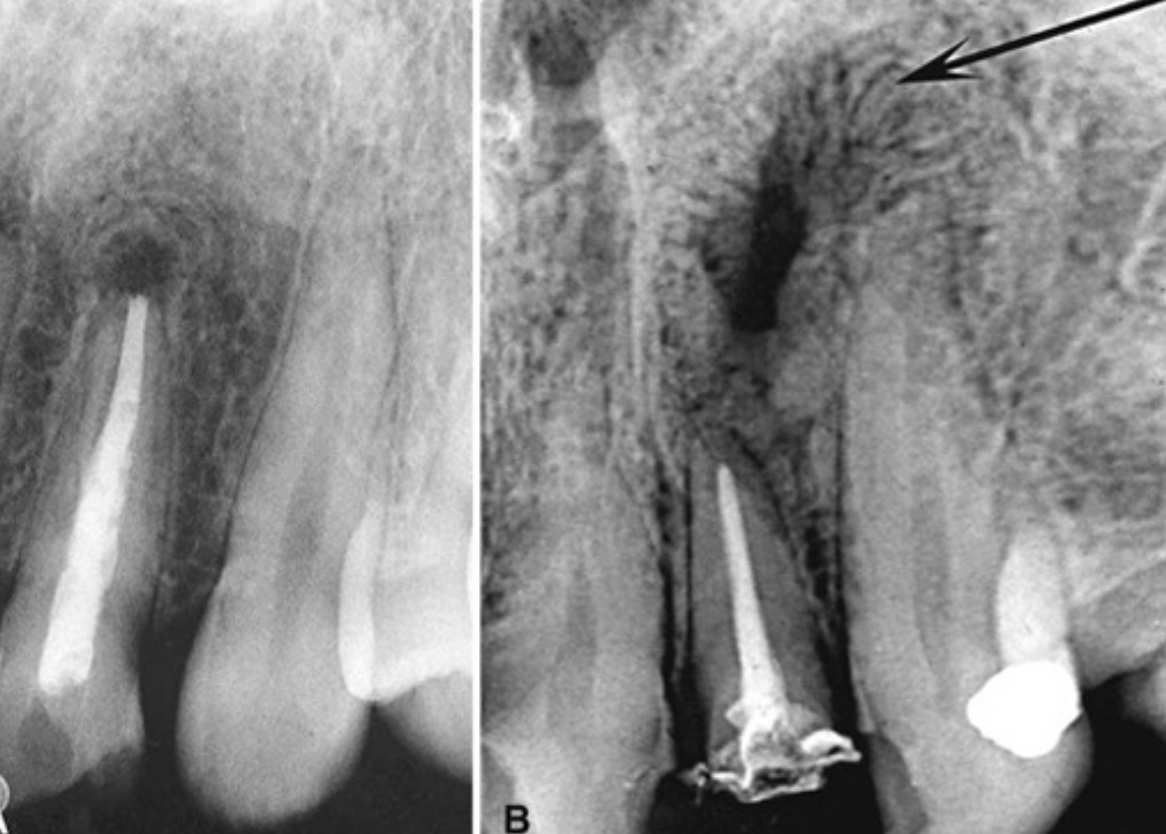

post-treatment changes

radiolucent areas may persist after successful orthograde or retrograde endodontics

central radiolucency may represent healing connective tissue

periophery may show granular bone or radiating trabeculae → “rolled border” or doughnut/fibrous scar pattern

rare cases

metastatic lesions or blood-borne malignancies may develop in periapical region

close inspection may reveal subtle cancellous bone destruction